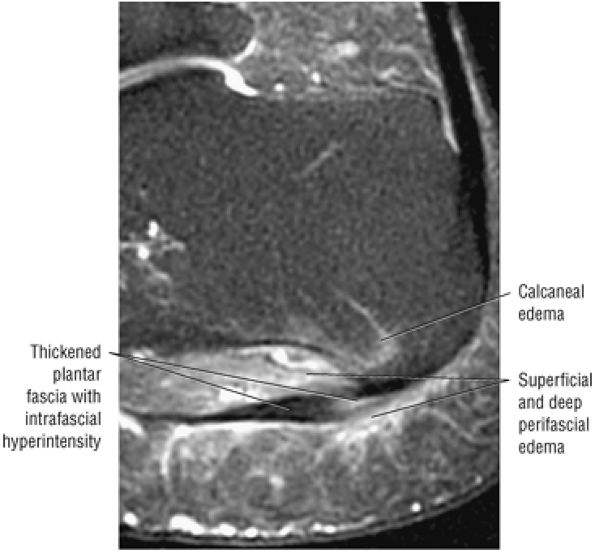

FIGURE 5.137 ● Normal MR appearance of the spring ligament complex. (A) Axial PD image demonstrates the lateral and intermediate calcaneonavicular ligaments originating from the notch between the anterior and middle articular facets of the calcaneus. The lateral calcaneonavicular ligament inserts on the navicular beak. (B) Axial PD image a few slices superior demonstrates the superomedial calcaneonavicular ligament deep to the posterior tibial tendon as it passes along the lateral aspect of the talar head toward its attachment to the dorsal aspect of the navicular tubercle. (C) Coronal T1-weighted image at the level of the talar head demonstrates the superomedial calcaneonavicular ligament deep to the posterior tibial tendon along the lateral aspect of the talar head.

|

![]() |

FIGURE 5.138 ● Pathologic appearances of the superomedial calcaneonavicular ligament. (A) Coronal FS PD image with fat saturation demonstrates a thickened and mildly edematous superomedial calcaneonavicular ligament in a patient who also had posterior tibial tendon strain. (B) Axial FS PD image with fat saturation demonstrates a thickened and edematous superomedial calcaneonavicular ligament in the setting of a partial posterior tibial tendon tear. (C) Axial PD image demonstrates a heterogeneous and irregular superomedial calcaneonavicular ligament in the setting of posterior tibial tendinosis and pes planus.